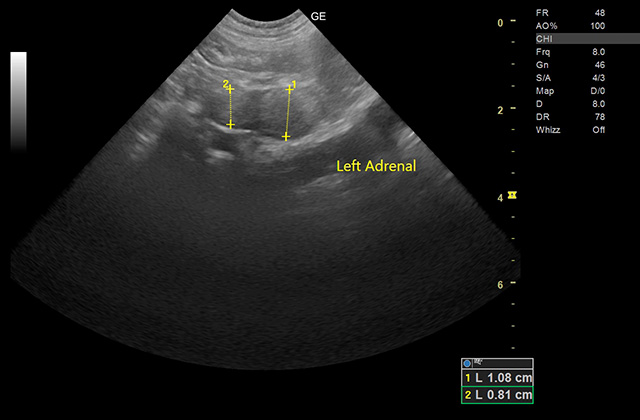

5エコー検査

エコー装置を使って臓器の形態異常や動き、腫瘍の有無を観察します。また、心臓の動きや血液の流れを検査します。

ラブラドール・レトリバー/8歳/副腎腫瘍

普段はアトピー性皮膚炎で当院に通っている患者様です。

8歳になったのきっかけに健康診断実施したところ、お腹の中の副腎に腫瘍があることが健康診断でわかりました。

大学病院で検査をしてもらったところ、この子は無症候性の副腎腫瘍と診断されました。副腎腫瘍は大きくなると周囲の血管を巻き込み、手術の難易度が高くなります。

幸い、この子は早期に発見できたため、お薬による治療と、定期的に副腎のサイズを超音波検査することで落ち着きました。

今回の子のように症状がなくても体の中で進行していく病気はたくさんあります。

重症化する前に、定期的な検査により病気を見つけ、治療をしていくことが健康寿命の延伸に繋がります。